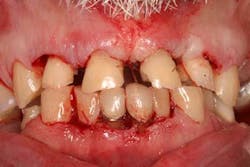

Case study A 58-year-old male with a noncontributory medical history presented to a private practice for a complete rehabilitation of his dentition due to years of bruxism and parafunction. (Fig. 1) After surgical and restorative consultations, a treatment plan was fabricated. The treatment plan included restoring his lost vertical dimension, restoring his natural dentition with porcelain-fused-to-metal full-coverage crowns, and replacing his lost posterior teeth with dental implants. After his vertical dimension was restored with an acrylic bite plate to a position harmonious with TMJ function, crown-lengthening surgery was performed. (Fig. 2)Fig. 2 Six weeks after, the teeth were temporized to develop soft tissue margins/interdental papillae. (Figs. 3 and 3a) The patient was kept in temporaries for three months, during which time an implant was placed in site No. 19. Both the natural dentition and the implant were completed at the same time, three months after implant placement. (Fig. 4) Because of the patient’s occlusal issues, the implant was screw-retained, and the patient was given a maxillary night guard. Three weeks after insertion, the patient presented with a loose abutment screw. The dentist tightened the screw and sent the patient home. This cycle was repeated two more times until the patient presented again with a loose crown, but this time, a fracture implant screw. The dentist attempted to remove the screw with a Cavitron and drilling the implant screw out to release preload, but to no avail. The case was then referred to my office for implant removal.

Fig. 3a